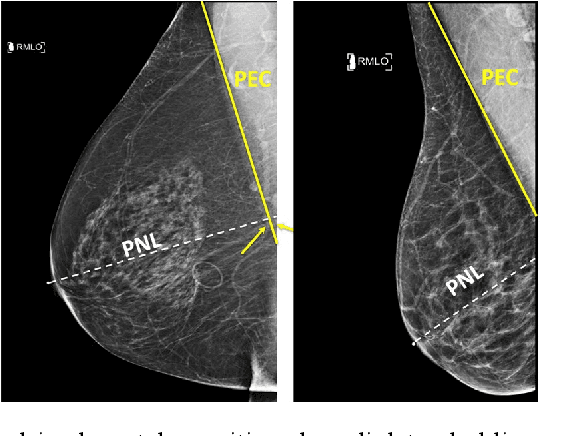

Abstract:Screening mammograms are a routine imaging exam performed to detect breast cancer in its early stages to reduce morbidity and mortality attributed to this disease. In order to maximize the efficacy of breast cancer screening programs, proper mammographic positioning is paramount. Proper positioning ensures adequate visualization of breast tissue and is necessary for effective breast cancer detection. Therefore, breast-imaging radiologists must assess each mammogram for the adequacy of positioning before providing a final interpretation of the examination; this often necessitates return patient visits for additional imaging. In this paper, we propose a deep learning-algorithm method that mimics and automates this decision-making process to identify poorly positioned mammograms. Our objective for this algorithm is to assist mammography technologists in recognizing inadequately positioned mammograms real-time, improve the quality of mammographic positioning and performance, and ultimately reducing repeat visits for patients with initially inadequate imaging. The proposed model showed a true positive rate for detecting correct positioning of 91.35% in the mediolateral oblique view and 95.11% in the craniocaudal view. In addition to these results, we also present an automatically generated report which can aid the mammography technologist in taking corrective measures during the patient visit.